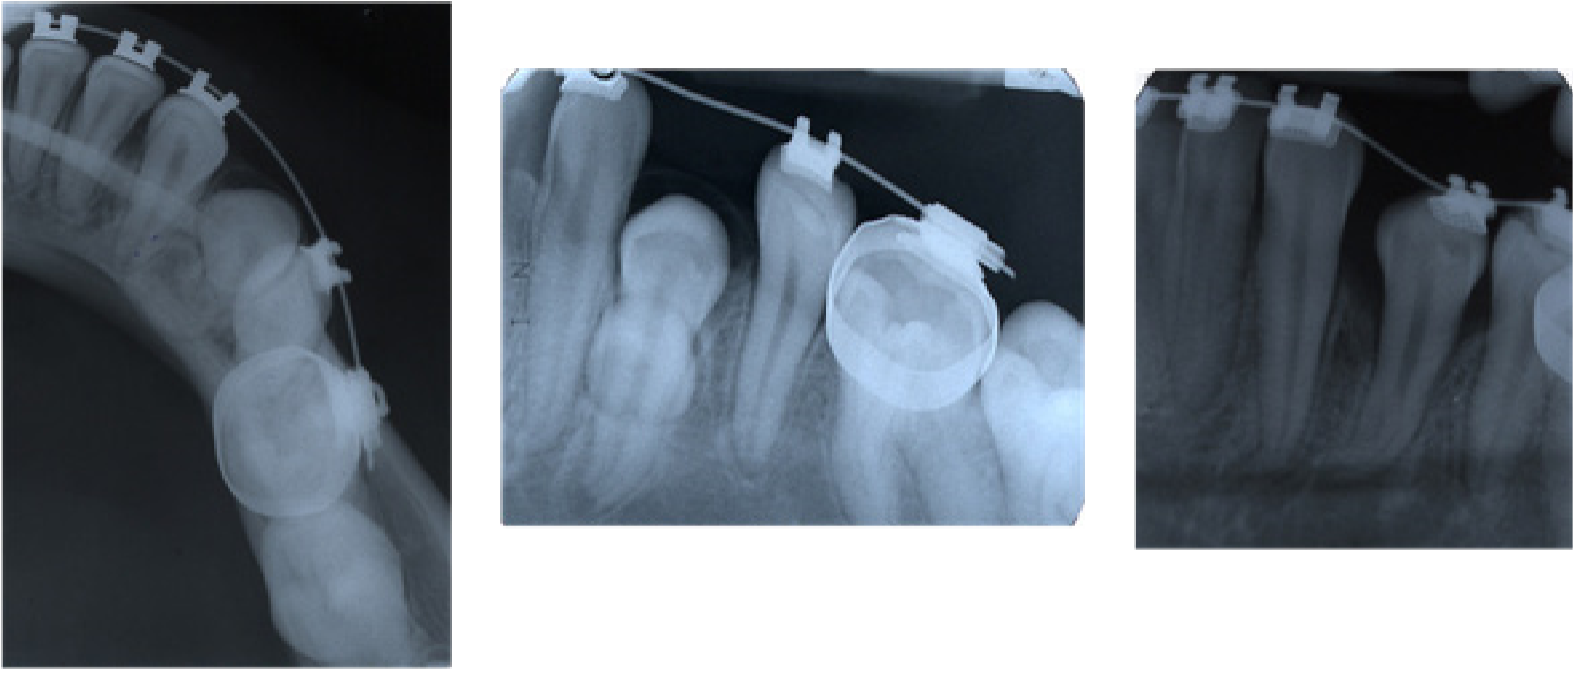

Caso 4. Paciente femenina de 13 años con diagnóstico de diabetes tipo I, con antecedente personal de intervención quirúrgica a los 18 meses por estrabismo ocular. Recibió tratamiento con expansor maxilar a los 8 años por mordida cruzada posterior. Madre reportó haber tenido ortodoncia, pero no recordó la causa, padre negó haber tenido ortodoncia aunque presentó apiñamiento. Los padres firmaron consentimiento informado. Al momento del diagnóstico la paciente presentó maloclusión Clase I con apiñamiento e impactación del primer premolar inferior izquierdo, asociado a diente supernumerario en la zona. El tratamiento consistió en ortodoncia correctiva, remoción del diente supernumerario, y la exposición quirúrgica del primer premolar inferior izquierdo impactado, para permitir traccionarlo al arco dentario (Figura 4).

Figura 4: Radiografía oclusal inferior inicial y radiografías periapicales de progreso de tracción del caso 4, mostrando la remoción del diente supernumerario y la resolución de la impactación del premolar inferior izquierdo, el cual termina con discreta dilaceración radicular.